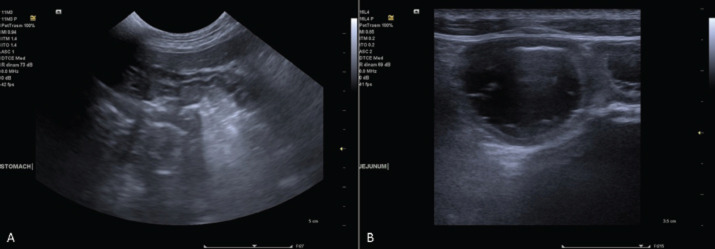

Case description: A 4-year-old, intact female German Shepherd was referred for a year-long history of anorexia, intermittent vomiting, and chronic diarrhea. She developed oral bleeding over the past 2 days. Diagnostic investigations revealed markedly prolonged prothrombin time (PT) and activated partial thromboplastin times (aPTT) with normal plasma fibrinogen levels. These findings, in conjunction with the normalization of PT and aPTT following vitamin K1 administration and the exclusion of rodenticide or coumarin intoxication, suggested vitamin K deficiency secondary to intestinal malabsorption. Further investigation led to the diagnosis of severe lymphoplasmacytic enterocolitis.